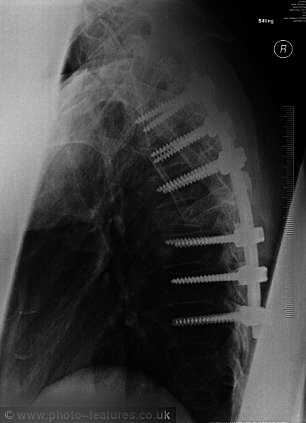

医生当时预言,马修斯可能救不回来,即便捡条命,今后也将无法行走。为拯救马修斯的性命,一周后,他被转至索尔福德皇家医院接受手术。医生用螺丝固定他的多处骨骼,并在他的背部安装钛金属棒,把他打造成真人版仿生人。